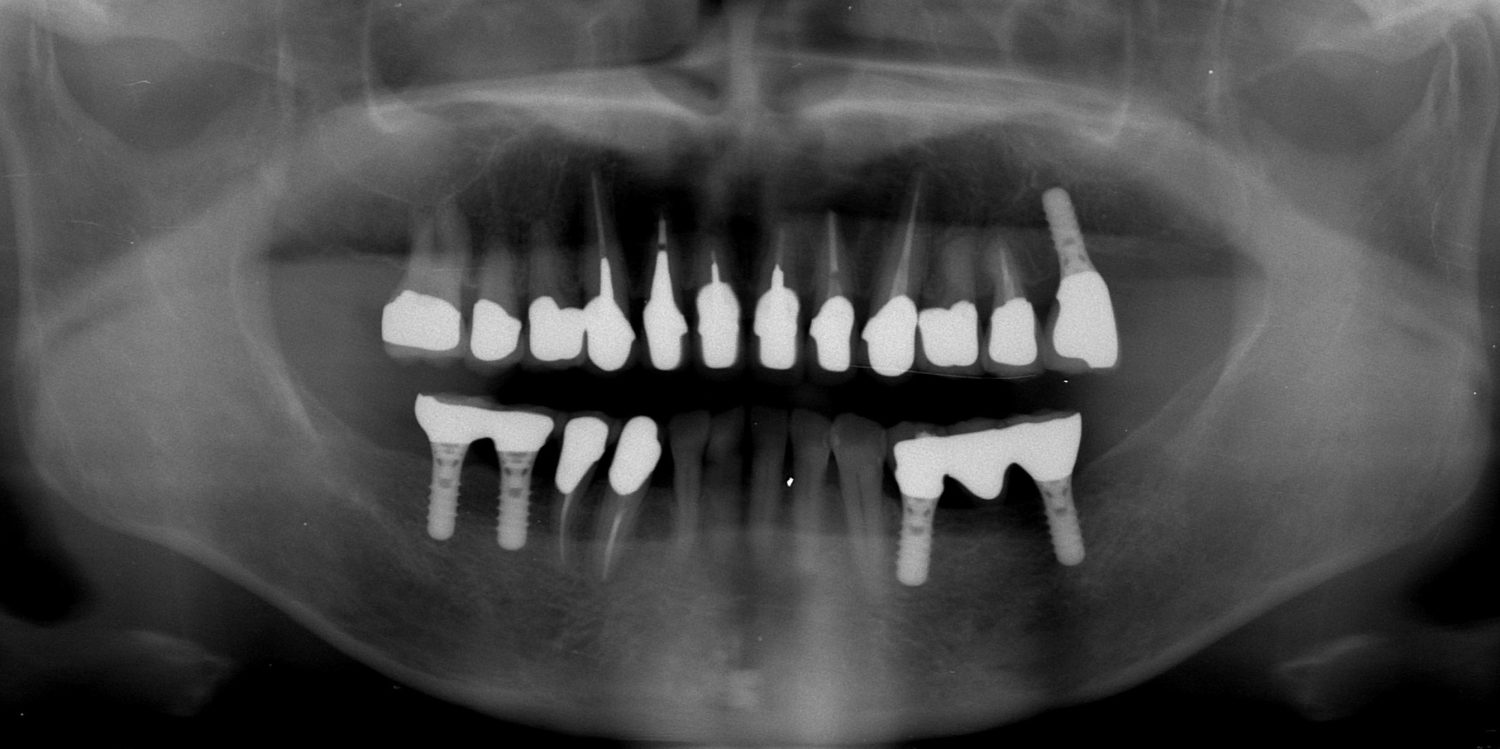

矯正治療・インプラント治療・セラミック治療・金属床(部分入れ歯)の症例紹介(三隅歯科クリニック)

三隅 賢祐(三隅歯科クリニック)

症例詳細

| 主訴 | 50代女性 以前いれた入れ歯が合わなくて使っていないので、しっかり噛めるようになりたい |

| 治療内容 | 矯正治療、インプラント治療、セラミック治療、金属床(部分入れ歯)を行いました。 |

| 治療費 | 4,200,000円(税込み) |

| 治療期間 | 2年(矯正治療期間 1年) |

| 治療回数 | 50回 |

| 想定されたリスク | 重度の歯周病で臼歯部の歯槽骨がかなり吸収していたため、インプラントが脱落するリスクがありました。 |